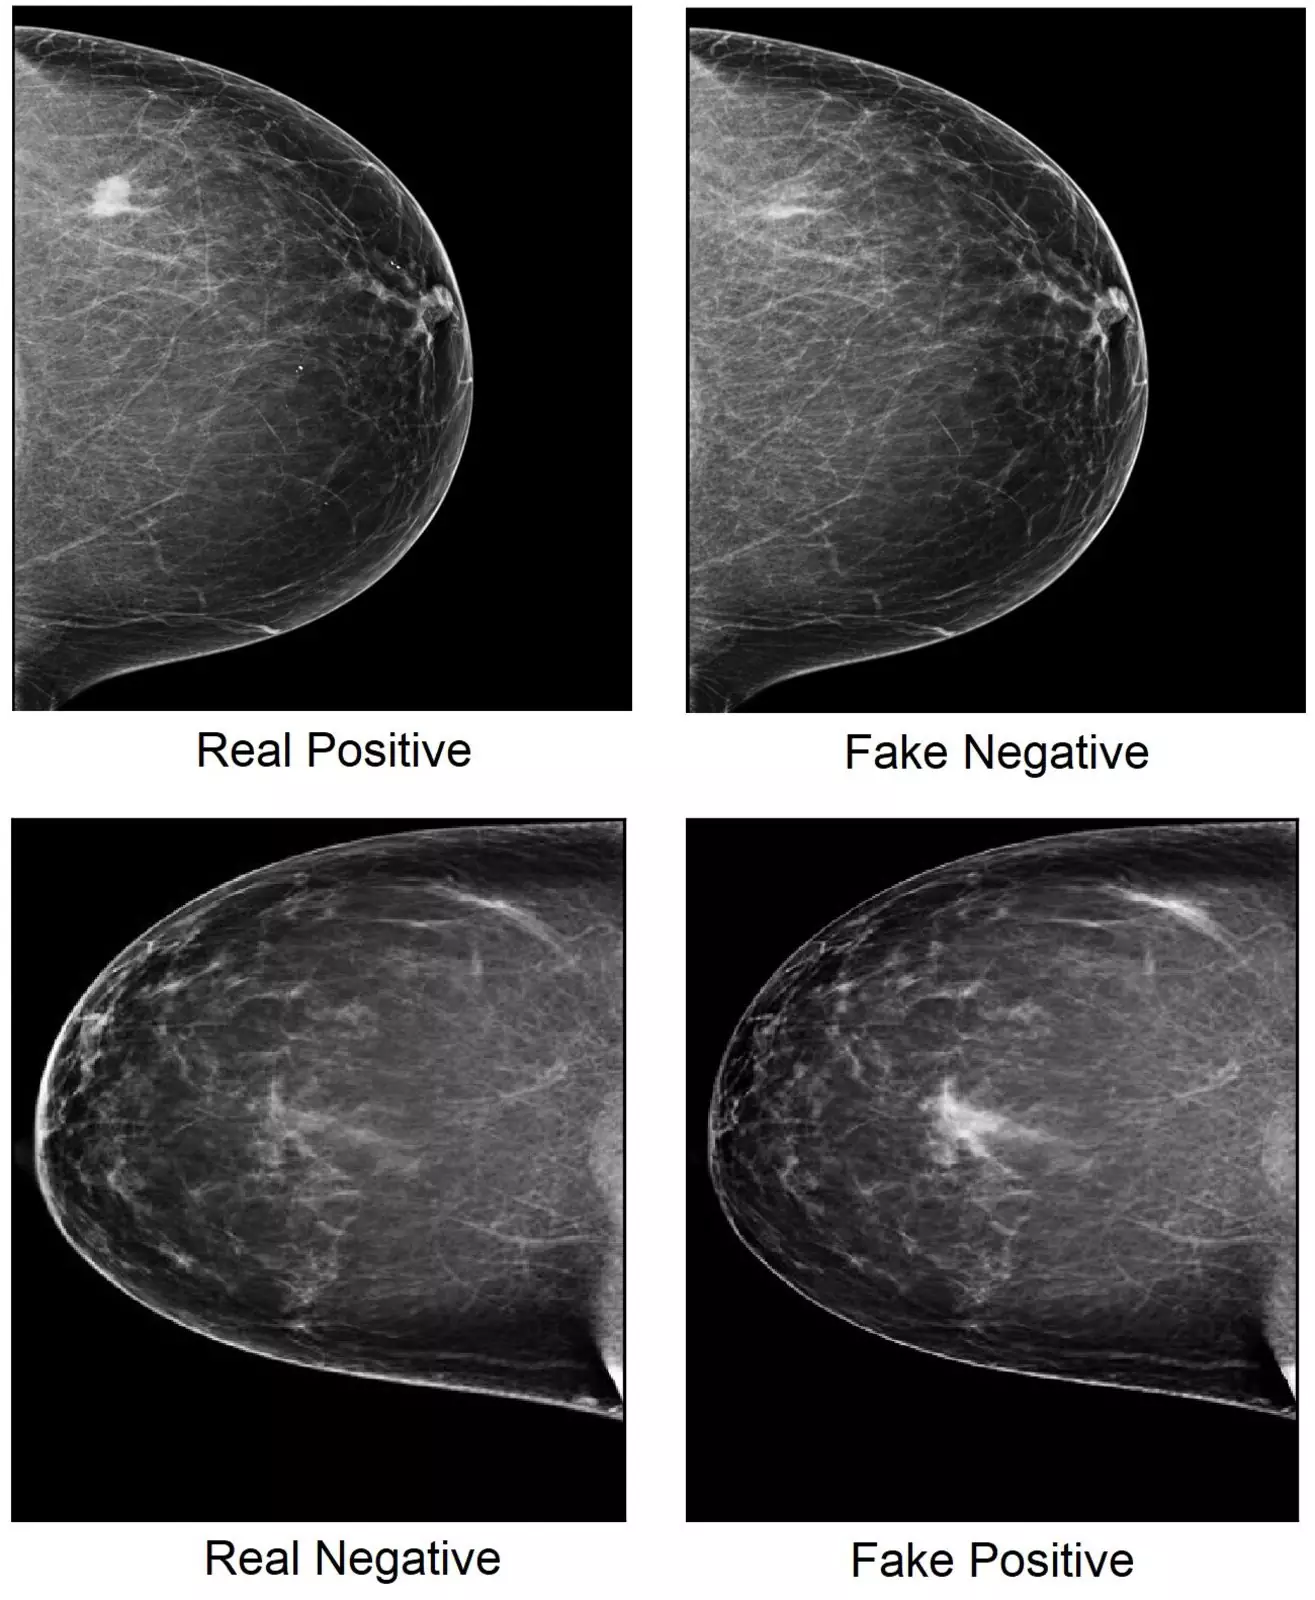

Кибератаки изменяют крошечные области изображений, которые влияют на решение ИИ, но незаметны для человеческого глаза. Это может привести к постановке ложноположительных диагнозов, — например, рака груди.

Враждебная программа при помощи манипуляций с крошечными областями пометила изображения как ложноотрицательные и ложноположительные.

Команда намеренно изменила изображения с маммограммой при помощи генеративно-состязательной сети (GAN) — нейросети, одна часть которой генерирует ложные изображения, чтобы вторая попыталась угадать правильные.

Затем эти изображения перемешели с настоящими и предложили ИИ просканировать их. В результате компьютер ошибся и ложно идентифицировал 69,1% фейковых изображений.

Во второй части эксперимента исследователи попросили пятерых радиологов определить, были ли изображения маммограммы настоящими или поддельными. Эксперты определили подлинность изображений с точностью от 29% до 71%, в зависимости от уровня подготовки специалиста.